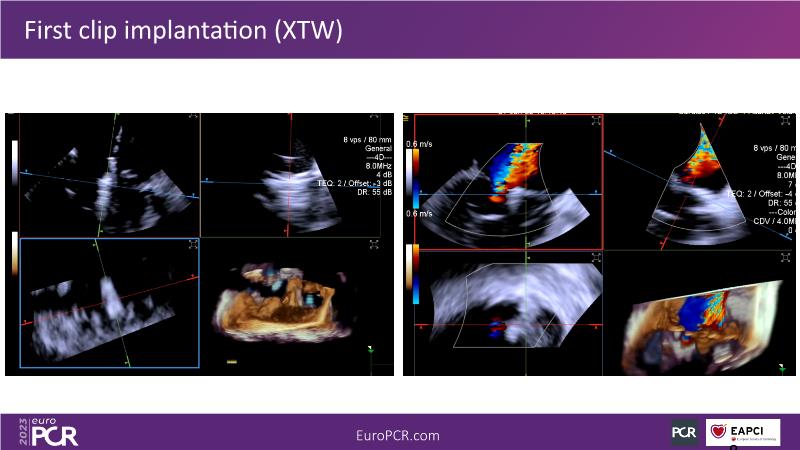

Use of 4D ICE in tricuspid and mitral valve interventions

Watch this session to know the challenges of TV imaging, to get an overview on 4D ICE technology, and to study both a transcatheter tricuspid valve procedure and a transcatheter mitral valve procedure through different case presentations, that will then be discussed.

- To get familiar with the 4D ICE technology and how it can support the imaging and guidance in complex structural heart disease interventions

- To understand the use of 4D ICE and benefits in tricuspid and mitral valve interventions